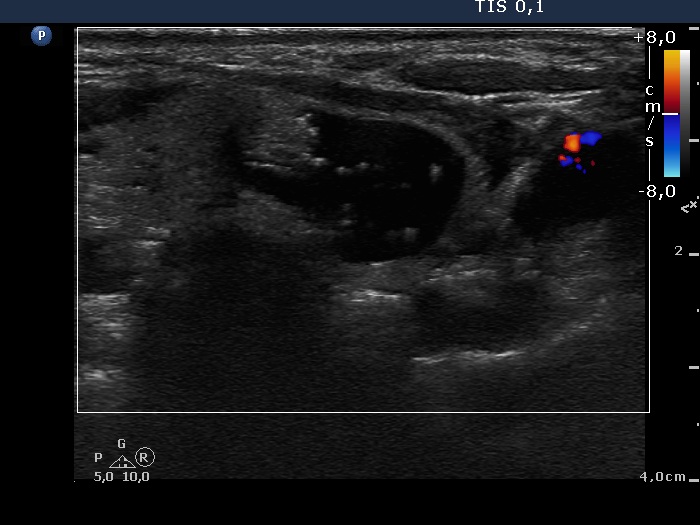

Right lobe, longitudinal scan

Left lobe, transverse scan, color Doppler mode. The lesion presents no vascularization.